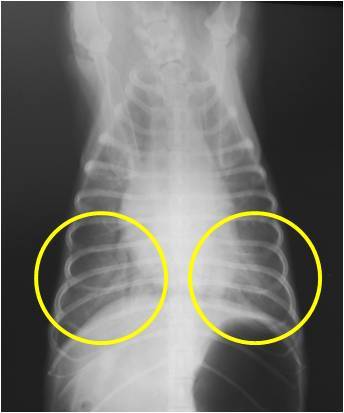

조금 확대를 하여서 보변 심한 폐수종을 확인 하실 수 있습니다 (노란색 원)

폐란 원래 공기로 차 있기 때문에 방사선 검사상에서 검게 보여야 하는데

폐의 앞쪽( 노란색 원이 없는 곳 )과 뒤쪽( 노란색 원)을 비교해보면

검은 부위와 하얀 부위가 구별되는 것을 보실 수 있을실 겁니다.

이런 검은 부위는 정상적인 기능을 하고 있는 폐이고

하얀 부위는 폐 안에 부종 또는 염증 떄문에 정상적인 기능을 하지 못하고 있는 상태라고 보시면 됩니다.